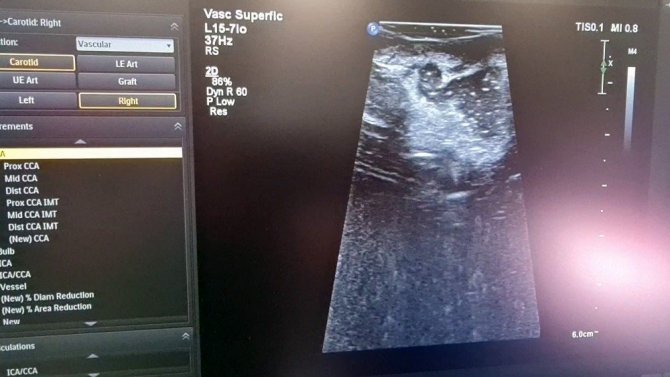

Ameliyathane de ilk ameliyat 27 yaşında beyninde tümör olan bir hastaya gerçekleştirildi. Uzun bir ameliyatın ardından hastanın ameliyatının tamamlandığı düşünüldü. Ancak ameliyatı gerçekleştiren Doç. Dr. Ömür Günaldı hastanın MR'ının çekilmesini istedi. Çekilen MR'da gözle ve ultrasonla görülmesi imkansız olan küçük bir tümör dokusunun kaldığı fark edildi. Hasta tekrar ameliyathaneye alındı ve ameliyata devam edilerek hasta da bulunan son parça da alınarak hastanın ameliyatı tamamlandı.

Bu yöntem ile yapılan ameliyatların çok daha güvenli bir cerrahi sağladığını belirten Beyin Cerrahi Kliniği İdari Sorumlusu Doç. Dr. Ömür Günaldı, "İntraoperatif MR da ilk beyin ameliyatımızı gerçekleştirdik. Önce ultrasonla görüntüledik daha sonra İntraoperatif MR çektirdik. Bu yöntem hasta için daha güvenli bir cerrahi sağlıyor. Bize de ameliyat esnasında sonucu değerlendirme imkanı tanımış oluyor" dedi.